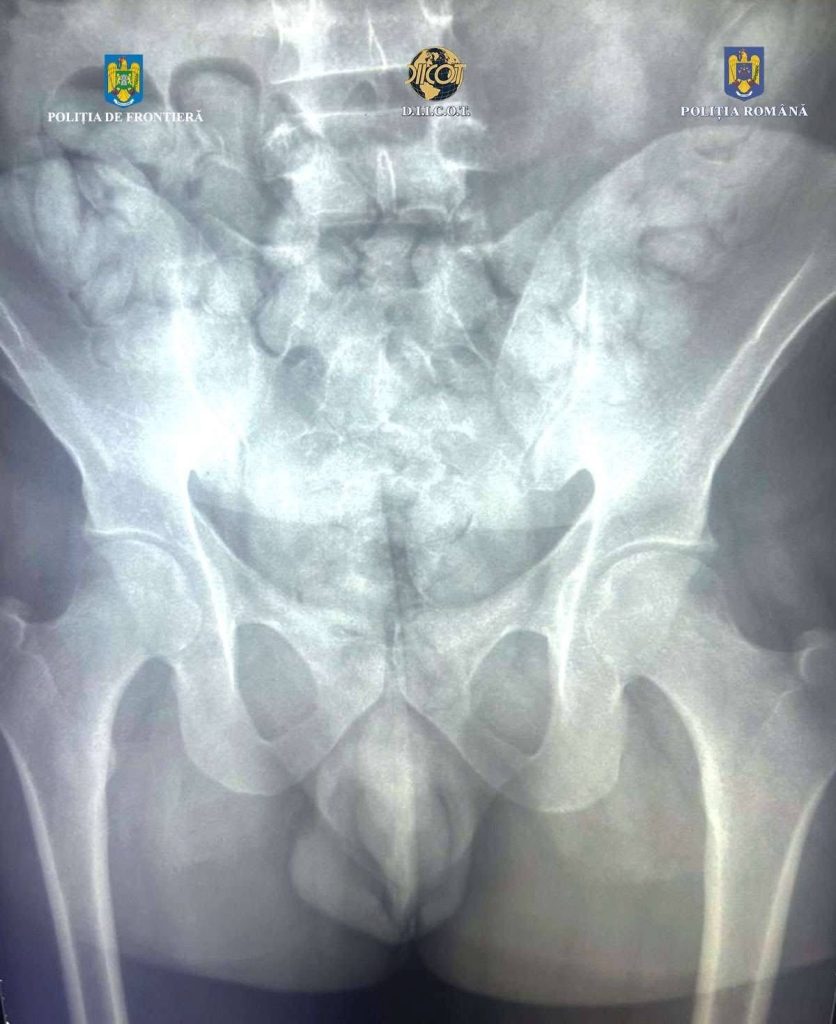

O nouă surpriză a venit însă la verificările cu scanerul corporal cu raze, X aflat în dotarea Poliției de Frontieră. În interiorul abdomenului, au fost observate mai multe formațiuni neobișnuite, care nu corespund anatomiei umane. Drept urmare, tânărul a fost condus la un spital, unde, pe parcursul internării, a eliminat 62 de cașete, ce conțineau aproximativ 350 de grame de substanță pulverulentă (în prezent aflată în curs de expertizare).